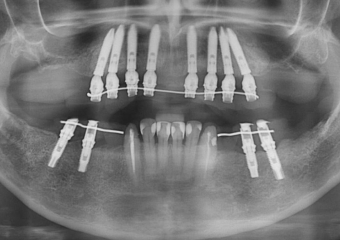

Raio X final